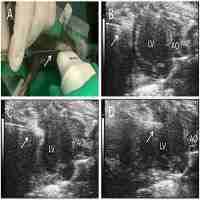

| Abstract | Although clinical trials of autologous whole bone marrow for cardiac repair demonstrate promising results, many practical and mechanistic issues regarding this therapy remain highly controversial. Here, we report the results of a randomized study of bone-marrow-derived mesenchymal stem cells, administered to pigs, which offer several new insights regarding cellular cardiomyoplasty. First, cells were safely injected by using a percutaneous-injection catheter 3 d after myocardial infarction. Second, cellular transplantation resulted in long-term engraftment, profound reduction in scar formation, and near-normalization of cardiac function. Third, transplanted cells were preprepared from an allogeneic donor and were not rejected, a major practical advance for widespread application of this therapy. Together, these findings demonstrate that the direct injection of cellular grafts into damaged myocardium is safe and effective in the periinfarct period. The direct delivery of cells to necrotic myocardium offers a valuable alternative to intracoronary cell injections, and the use of allogeneic mesenchymal stem cells provides a valuable strategy for cardiac regenerative therapy that avoids the need for preparing autologous cells from the recipient. |